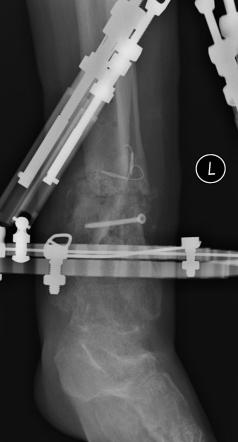

Postoperative (12th) images of left ankle

The images displayed here were created at various appointments following surgery performed by Dr. Daniel Saunders. In the X-Ray you can see

where Dr. Saunders has removed the fibula plate, joined the tibia and fibula with a screw, built-up the area of the tibia where previously

there was considerable absence of bone and lastly added the EBI OsteoGen-M Bone Stimulator (dual lead). The photos show the left side site

where the fibula plate was removed, the top site where donor bone, bone filler material and the stimulator were added and the right side

where the tissue has burst because of swelling. Liam was placed on an IV drip of Vancomycin following surgery to combat the potential onset

of Osteomyelitis. The image of the cast includes the fibula plate that was removed during surgery. The next images were taken later and show

that the staples and stitches were removed. In one of the images, you can see Liam's wife Madeline helping with leg cleanup and in one image

can be seen the EBI representative after being put to work (holding up the left leg while the latest cast cures) by Dr. Saunders. Later shots show

a healing tissue burst site with some overgrowth and Dr. Saunders cauterizing the overgrowth. Bones shifting too much (shown in X-Rays). The

last images are of the left ankle prior to the 13th surgery.